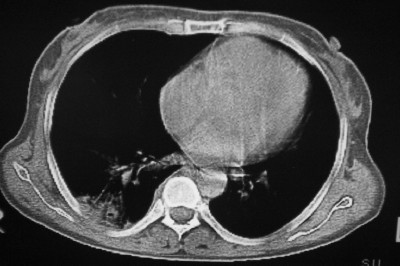

以下是引用天南地北在2007-4-10 1:49:00的发言:[br]考虑右下叶周围型肺癌伴肋骨转移。

以下是引用jone-baby在2007-4-10 8:45:00的发言:[br][br] [br] 患者[br]有发热史,x线片考虑肺脓肿.肺脓肿可以导致肋骨破坏吗?[br]脓肿可以排除吗? [br] [br] [br]

以下是引用林建春在2007-4-10 7:35:00的发言:[br]周围型肺癌侵犯肋骨

以下是引用liuyue在2007-4-10 7:56:00的发言:[br]周围型肺癌侵犯肋骨,左肺转移。

以下是引用zhangzhongshou在2007-4-10 10:24:00的发言:[br]右肺下叶背段厚壁空洞,伴胸膜改变、肋骨破坏,其内可见死骨、周围骨质硬化,左肺可见小结节影,[br]单纯影像学更支持结核。建议进一步检查。